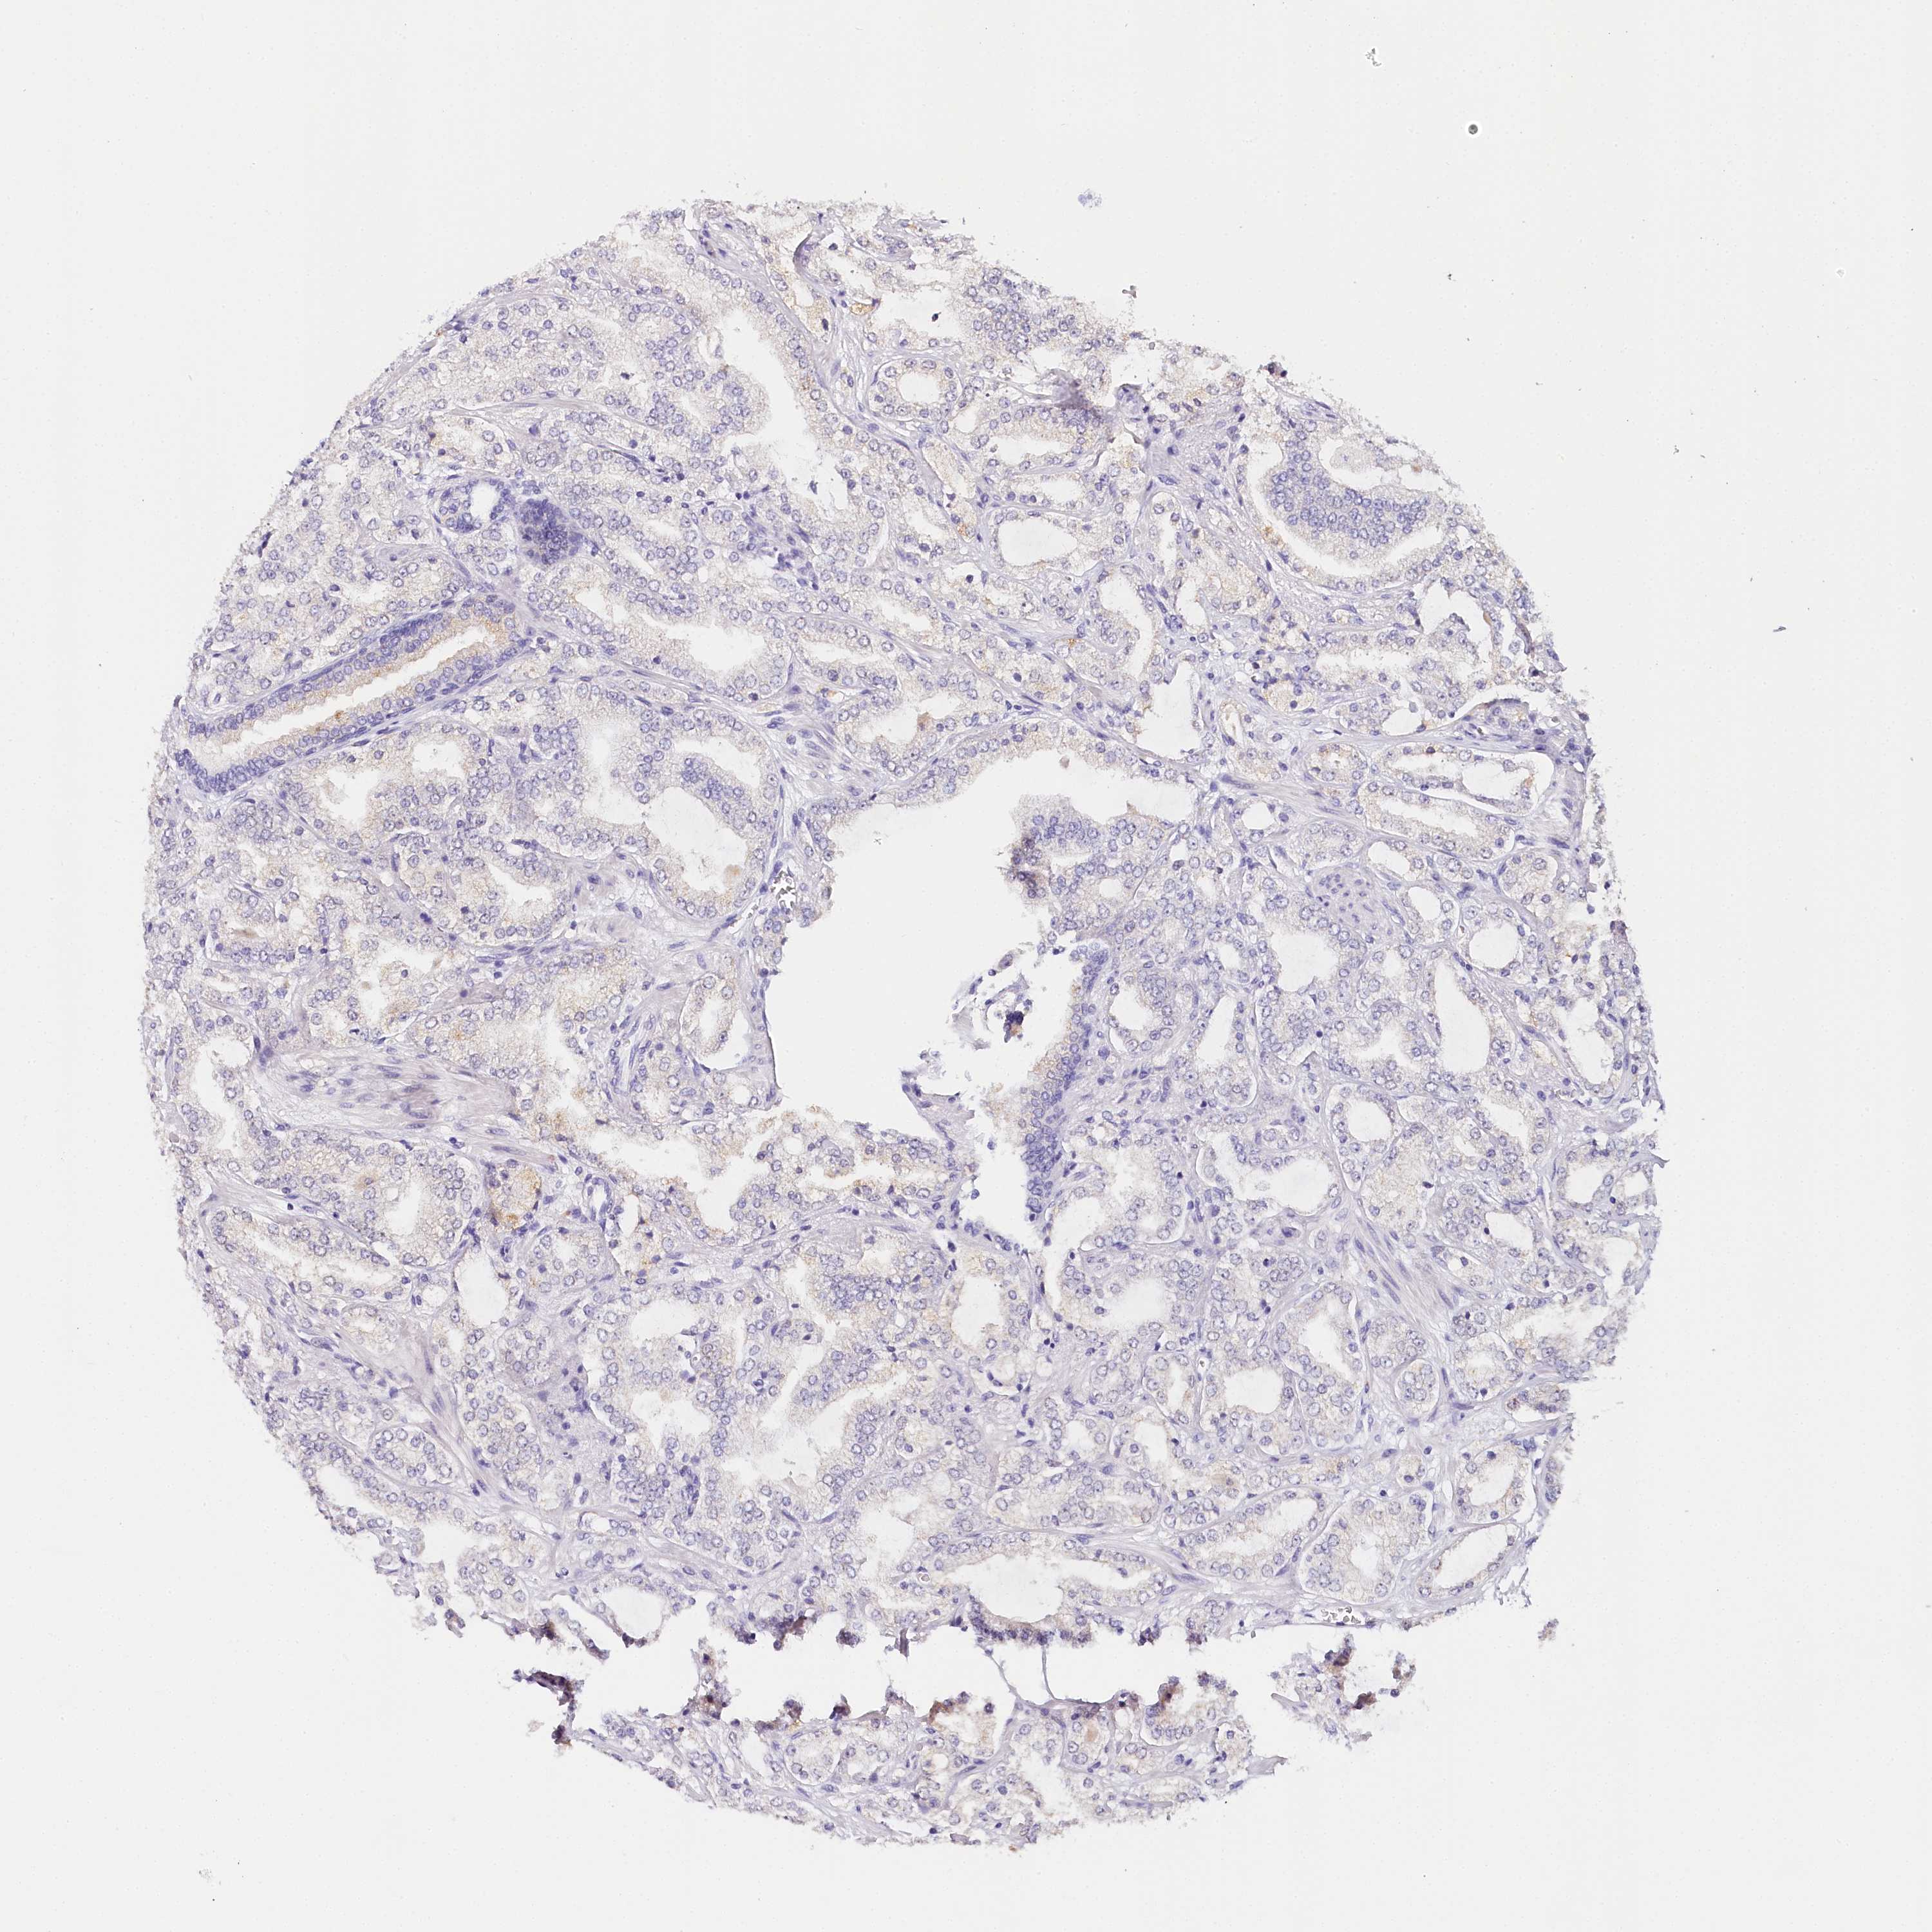

PROSTATE CANCER - Protein expressioni

A mouse-over function shows sample information and annotation data. Click on an image to view it in a full screen mode. Samples can be filtered based on level of antibody staining by selecting one or several of the following categories: high, medium, low and not detected. The assay and annotation is described here.

Note that samples used for immunohistochemistry by the Human Protein Atlas do not correspond to samples in the TCGA dataset.

Antibody stainingi

Antibody staining in the annotated cell types in the current human tissue is reported as not detected, low, medium, or high, based on conventional immunohistochemistry profiling in selected tissues. This score is based on the combination of the staining intensity and fraction of stained cells.

Each image is clickable and will lead to virtual microscopy that enables deeper exploration of all samples and also displays staining intensity scores, fraction scores and subcellular localization as well as patient and tissue information for each sample.

Antibody CAB002973

Antibody CAB039238

Antibody CAB039239

Antibody CAB072876

Staining

High

Medium

Low

Not detected

Intensity

Strong

Moderate

Weak

Negative

Quantity

>75%

75%-25%

<25%

None

Location

Nuclear

Cytoplasmic/membranous

Cytoplasmic/membranous,nuclear

Adenocarcinoma, Low grade

Adenocarcinoma, Medium grade

Adenocarcinoma, High grade

Adenocarcinoma, NOS